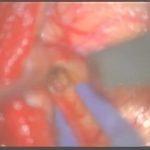

摘出 前